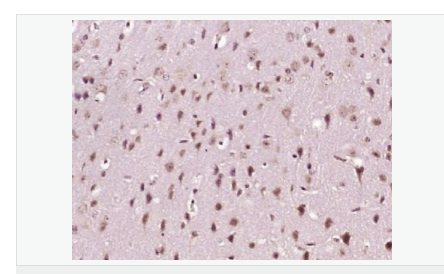

| 產(chǎn)品應(yīng)用 | WB=1:500-2000 IHC-P=1:100-500 IHC-F=1:100-500 ICC=1:100-500 IF=1:100-500 (石蠟切片需做抗原修復(fù)) not yet tested in other applications. optimal dilutions/concentrations should be determined by the end user. |